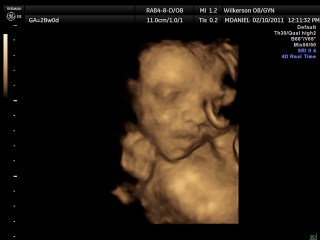

We had our 4-D ultrasound today. James would not cooperate at all but Jackson did. He was so precious he kept his hand over his face though. It was so neat. They are definitely cramped in there. We go back Monday and hopefully James will work with us. Here our a few pictures we have more but they are video rather than pictures.

Here is sweet Jackson: